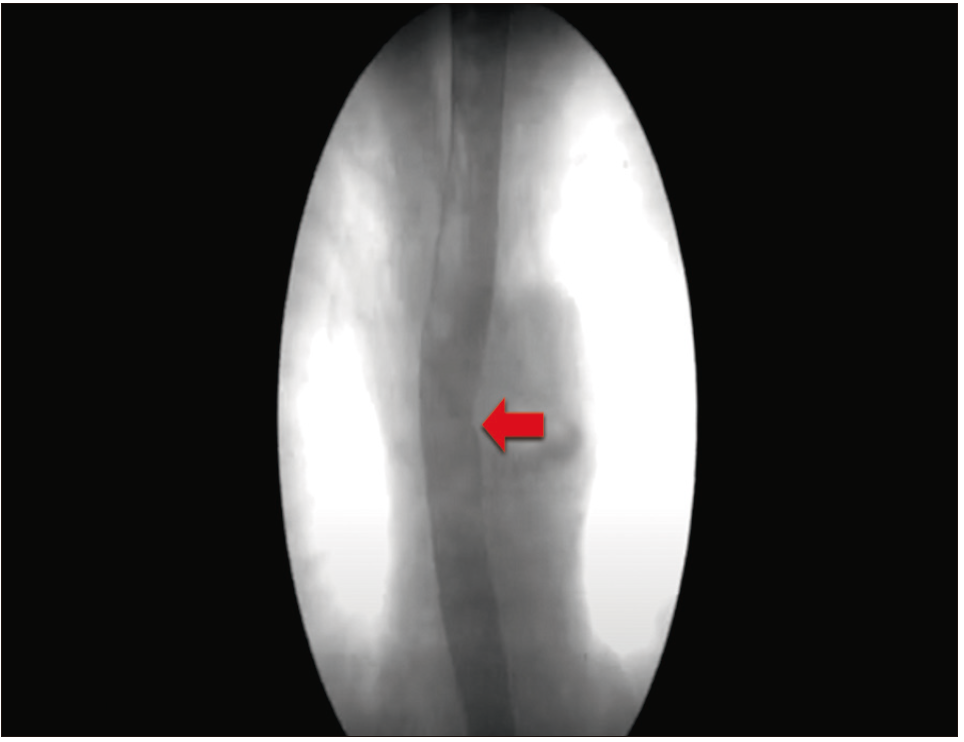

Dado que el paciente presentaba síntomas intermitentes con características de disfagia funcional se realizaron estudios dinámicos para correlacionar los hallazgos en las imágenes con la disfagia. El esofagograma baritado evidenció una impronta en el tercio proximal del esófago con adecuado vaciamiento del contraste (Figura 2). Luego se realizó una HREM (Laborie/Diversatek system) con 8 horas de ayuno mediante un catéter de estado sólido con 36 sensores y sin medicación que pudiera alterar la motilidad esofágica. Se realizaron 10 degluciones con 5 ml de solución fisiológica en posición semiacostada y 5 en sedestación. El cuerpo esofágico presentó un vigor contráctil aumentado, con 30% de contractilidad distal integrada > 8000 mmHg/s/cm, con una mediana de presión de relajación integrada de 21 mmHg (normal en Diversatek < 22 mmHg). Se diagnosticó un esófago hipercontráctil de pico simple (Figura 3). Como complemento, se realizó la prueba de deglución rápida múltiple (5 degluciones de 2 ml de agua con menos de 3 segundos de diferencia) que evidenció una adecuada inhibición deglutoria y una buena reserva peristáltica. El desafío rápido con los tragos líquidos (ingesta de 200 ml de agua en el menor tiempo posible) no pudo completarse por la presencia de dolor torácico. Para la evaluación del reflujo gastroesofágico se realizó una pH impedanciometría off IBP que no mostró exposición ácida patológica, episodios de reflujo patológicos ni asociación sintomática. Teniendo en cuenta la presentación intermitente de la disfagia con adecuado vaciamiento del contraste en el esofagograma baritado y la presencia de esófago hipercontráctil en la HREM, se interpretó que los síntomas estaban vinculados al trastorno motor. Se realizó tratamiento con inyección de toxina botulínica (100 U) en el cuerpo esofágico y disminuyeron los síntomas.

Figura 2. El esofagograma baritado muestra una compresión externa en

el tercio superior del esófago